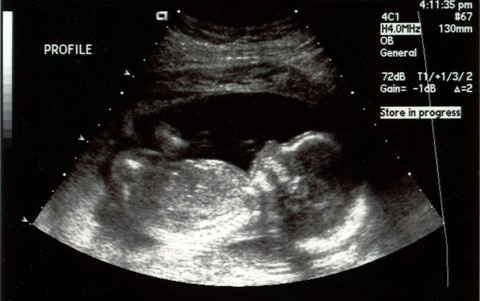

An ultrasound image of a baby, seen in profile.

This image is almost exactly a month old now, but there she is, our baby girl.* That’s her at 20 weeks. I haven’t ever been this excited to meet anyone, ever. Expect a lot more baby-centric posts around early February.

*We’re close to 100% positive the baby is a girl.